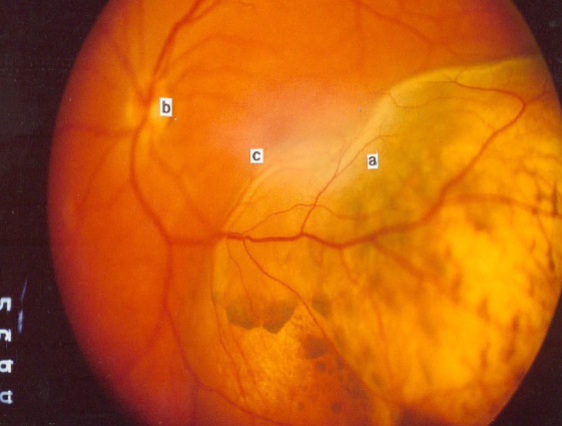

metastatic carcinoma of choroid

more common than primary malignancies

seed of cancer that started in a cancer elsewhere & spread to eye via blood flow

features:

cream, yellow, light brown

flat or slightly elevated mottled pigment clumping on surface

extensive exudative RD

maybe multifocal or bilateral

testing:

B scan: diffuse choroidal thickening

tx:

no enucleation unless painful

chemo

external beam radiation

breast

what is the most frequent primary site for metastatic carcinoma of the choroid for females?

lungs

what is the most frequent primary site for metastatic carcinoma of the choroid for males?

choroid

what is the most common site for metastasis?

metastatic carcinoma

metastatic carcinoma

metastatic carcinoma

metastatic carcinoma

metastatic carcinoma

metastatic carcinoma

metastatic carcinoma

metastatic carcinoma

metastatic carcinoma